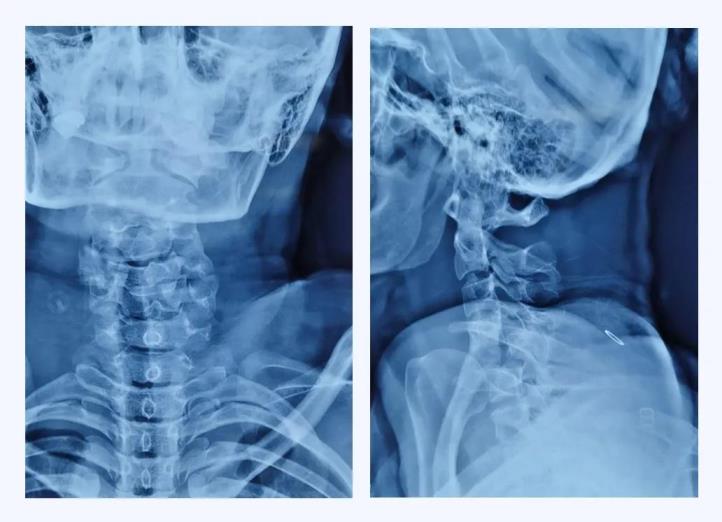

經(jīng)查,病人確診為“頸椎骨折脫位 、頸髓高位損傷四肢癱”,以致四肢感覺(jué)運(yùn)動(dòng)均喪失。第五頸椎椎體完全脫位于后方椎管內(nèi),頸脊髓損傷嚴(yán)重,這類(lèi)損傷導(dǎo)致脊髓水腫向上蔓延,可殃及呼吸循環(huán)控制中樞,患者隨時(shí)都有呼吸循環(huán)驟停危及生命的風(fēng)險(xiǎn)。我院骨科首席專(zhuān)家、業(yè)務(wù)院長(zhǎng)喬建民教授聞?dòng)嵹s到醫(yī)院進(jìn)行緊急救治。一般的頸椎骨折脫位,只需將脫位的椎體復(fù)位并固定即可,但該患者由于脫位的第5頸椎椎體完全脫位至椎管內(nèi),導(dǎo)致相應(yīng)節(jié)段頸脊髓受到嚴(yán)重?cái)D壓、損毀、變形,已無(wú)法手術(shù)將其復(fù)位,只能選擇切除。手術(shù)部位是高位頸脊髓神經(jīng),并緊鄰椎動(dòng)脈,稍有不慎就會(huì)加重?fù)p傷,危及生命。手術(shù)難度之高、風(fēng)險(xiǎn)之大,是可想而知的。要完成這臺(tái)如此高難度的手術(shù),不單單是對(duì)術(shù)者技術(shù)能力的考驗(yàn),更是對(duì)醫(yī)者心智和意志的挑戰(zhàn)。

術(shù)前X線(xiàn)